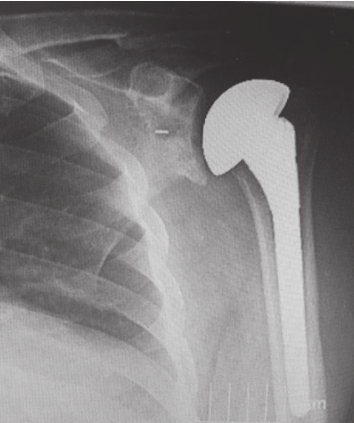

1) A hemi-arthroplasty is a partial shoulder replacement in which only the humeral head (ball) is replaced with a metallic

ball. This procedure is usually reserved for the treatment of fractures

of the humeral head which cannot be fixed with a plate and screws, as

well as for patients who are relatively young, where preserving bone for

possible revision surgeries later in life may be an advantage.